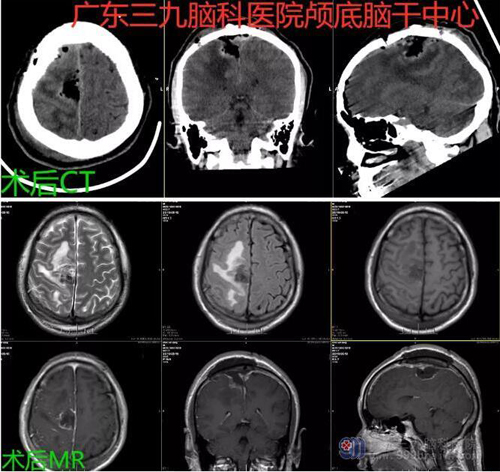

图2:术后CT及MR示右侧顶部术后改变,原病变已切除